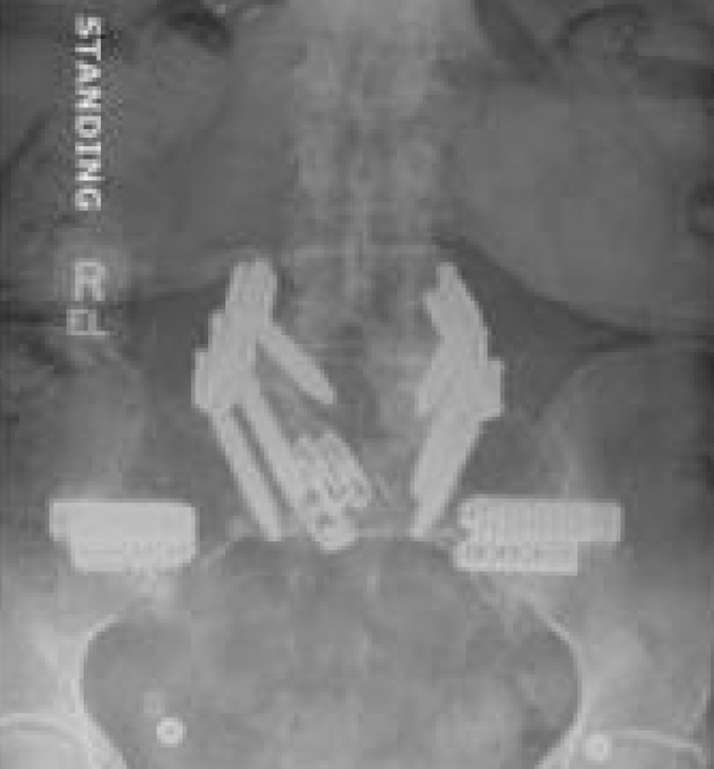

Bilateral Sacroiliac Joint Dysfunction Following L4-S1 Fusion

Patient Case History:

- High lumbar lordosis (77°) & pelvic incidence (86°)

- Spinal stenosis (L4-5) & radiculopathy (L5-S1)

- L4-5 & L5-S1 MIS transforaminal interbody fusion, November 2017

- Revision open L4-S1 fusion for pseudoarthrosis and hardware loosening, March 2019

- Bi-lateral SI joint degeneration with pain post revision surgery verified via SI joint block injection.

- Bilateral SI joint fusion using the iFuse 3D™ Implant System, August 2020